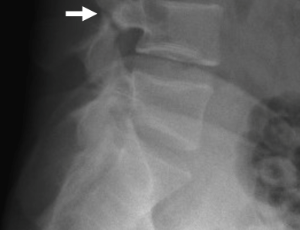

L4 Spondylolysis in a Young Adult: Selective Imaging and Conservative Management

Spondylolysis, a defect of the pars interarticularis, is a frequent cause of low back pain in young adults. A 19-year-old male presented with a year of chronic pain that recently worsened, limiting ambulation. He denied trauma, fever, neurological symptoms, or bowel/bladder dysfunction. Examination revealed an antalgic gait without focal tenderness or deficits. Given the underlying chronicity and functional limitation in a young patient, lumbar radiographs were obtained, which demonstrated a pars defect at L4.

Arch Med Case Rep, 2025, Volume 7, Issue 1, p31-33 | DOI: 10.33696/casereports.7.039